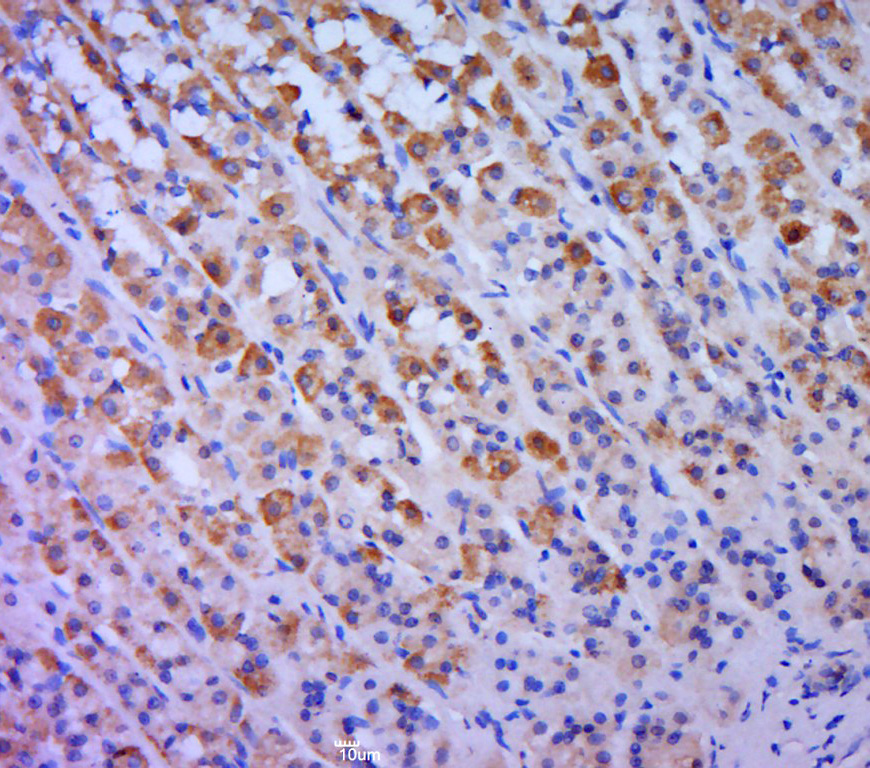

Paraformaldehyde-fixed, paraffin embedded (rat stomach tissue); Antigen retrieval by boiling in sodium citrate buffer (pH6.0) for 15min; Block endogenous peroxidase by 3% hydrogen peroxide for 20 minutes; Blocking buffer (normal goat serum) at 37°C for 30min; Antibody incubation with (PDE4A) Polyclonal Antibody, Unconjugated (bs-10140R) at 1:400 overnight at 4°C, followed by a conjugated secondary (sp-0023) for 20 minutes and DAB staining.